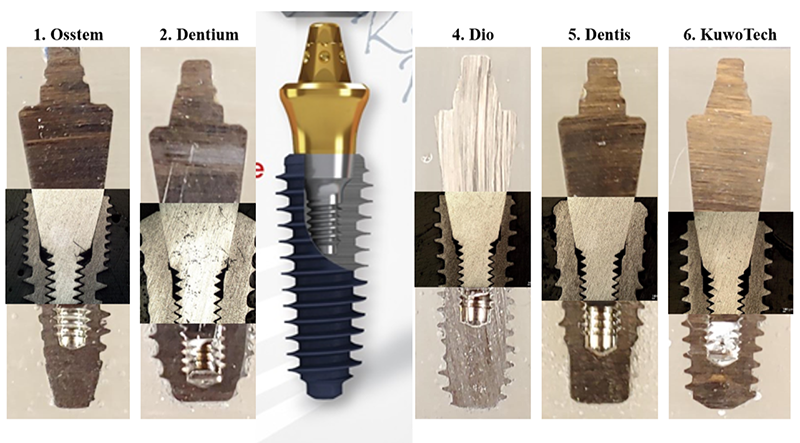

각각의 픽스쳐에 맞는 Ezc abutment를 제작해서 서로 호환되게 해 놨다.

Ez lock overdenture

system 때부터 각 픽스쳐에 맞게 abutment 를 만들어 왔다.

• fixture 내부 속으로 체결되는 abutment 때문에 생기는 구조적 한계로 어벗먼트와

픽스쳐의 파절 가능성이 비교적 높다는 최대 단점을 갖고 있다.

이렇게 찢어지는 것을 보완하기 위해서 나온 임플란트가 소위 스트라우만의 ITI implant다. Bone level에서 gingiva level로 올라오면서 픽스쳐 두께가 강화된 것이다.